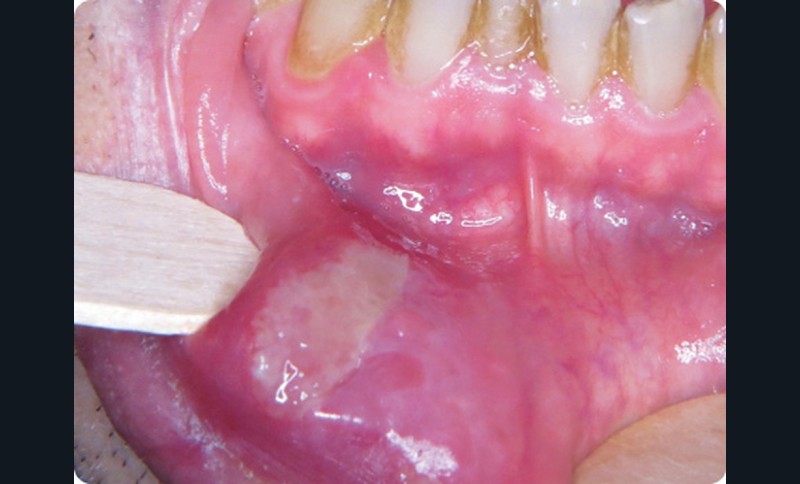

- Le patient présentait une ulcération de la partie muqueuse de la lèvre inférieure, latéralisée à droite. L’ulcération, de couleur jaunâtre, mesurait 1,5 cm par 3 cm. Les bords n’étaient pas surélevés et avaient une couleur rouge (inflammation) ou blanchâtre (œdème épithélial).